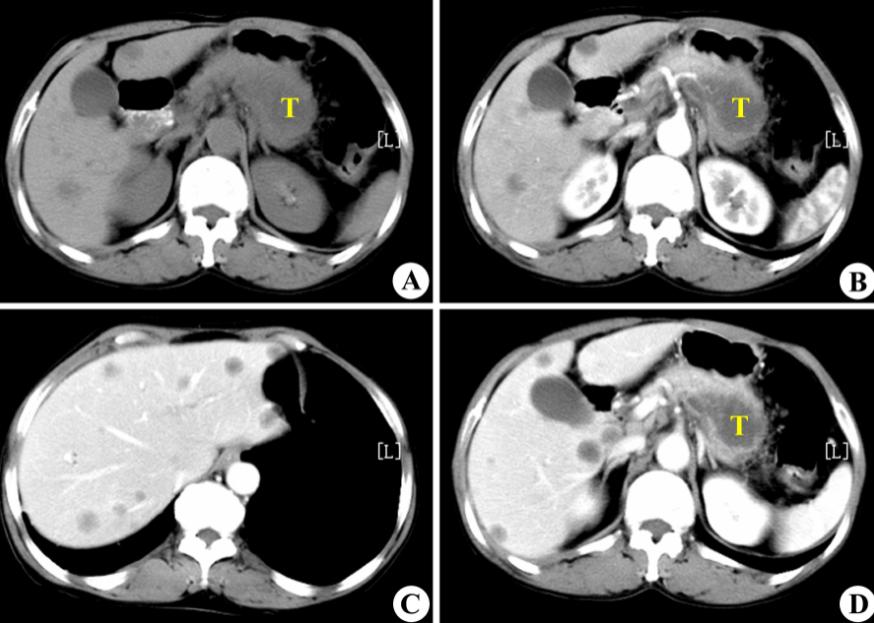

去年4月,本来只是因为一点小咳嗽,去医院做了个常规的CT平扫,没想到这一扫,黄女士竟然被AI识别成了疑似早期胰腺癌。

返回医院复查后,AI的判断果然是对的:胰尾部真的有肿块!

在使用对比剂进行增强扫描后,确定其大小为25×31mm。这大约是一颗中等大小的葡萄那么大。

在前面提到的阿里所使用的PANDA模型中,最重要的一个技术,就是一种叫做“图像配准”的技术,将对比增强CT上的病变标注“复制”到非对比CT图像上。

用直观的语言来描述,这种做法就是:先找两张CT图片,其中一张是普通CT,另一张是增强CT,之后,PANDA通过将两张CT“重叠”在一起的办法,来将增强CT上的病变区域准确地映射到普通CT的相应位置上。